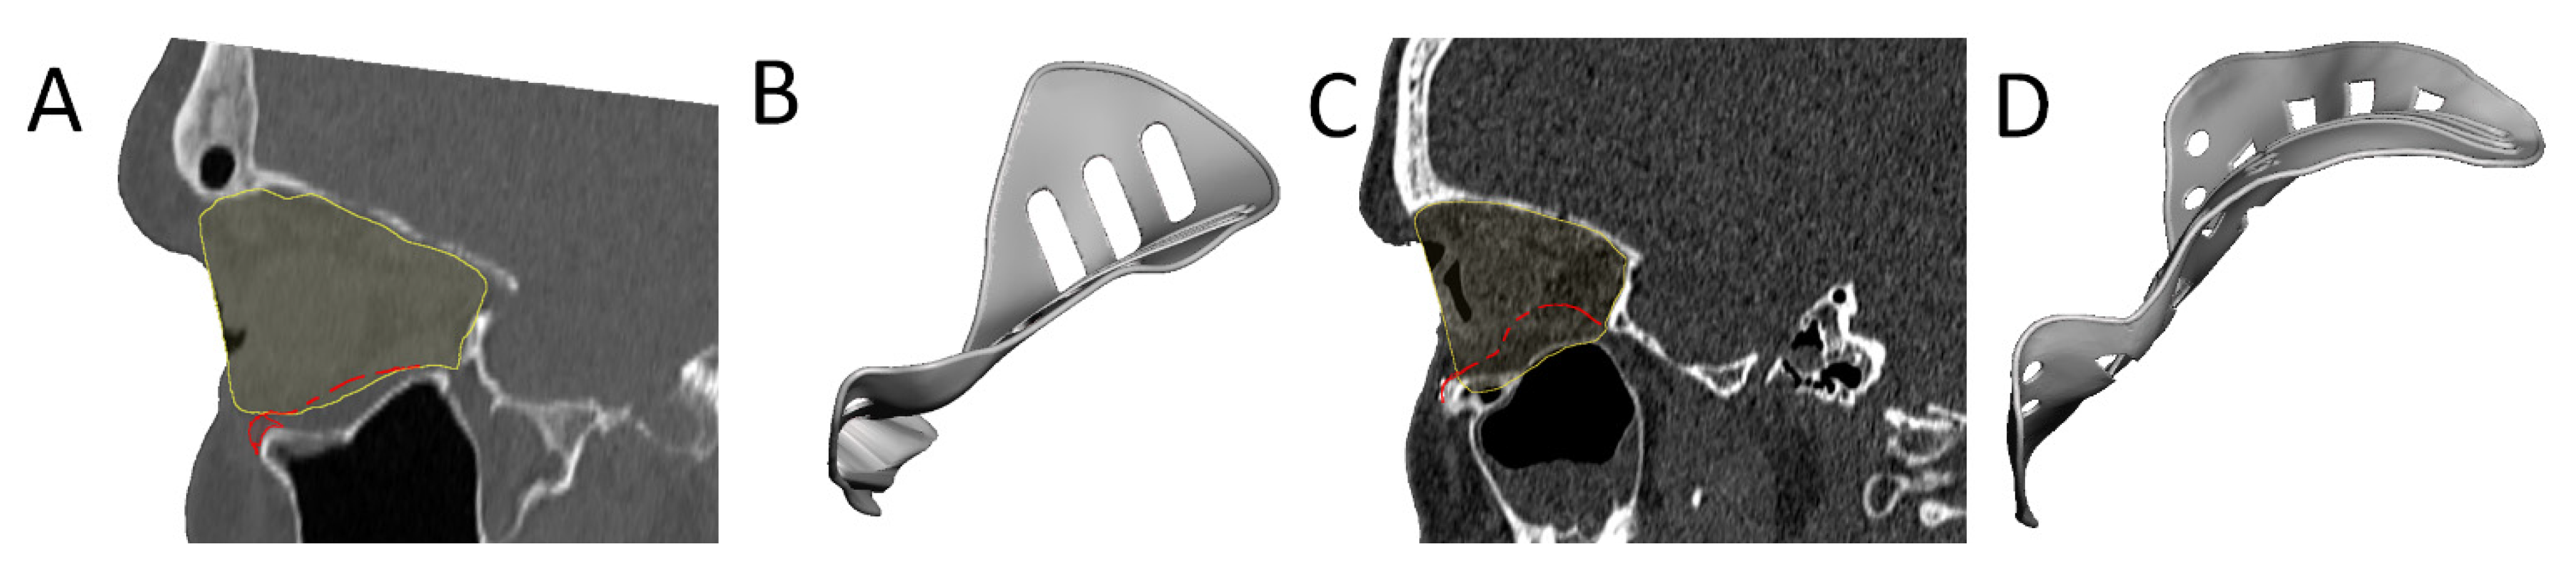

2.4. Patient-Specific Implant Design